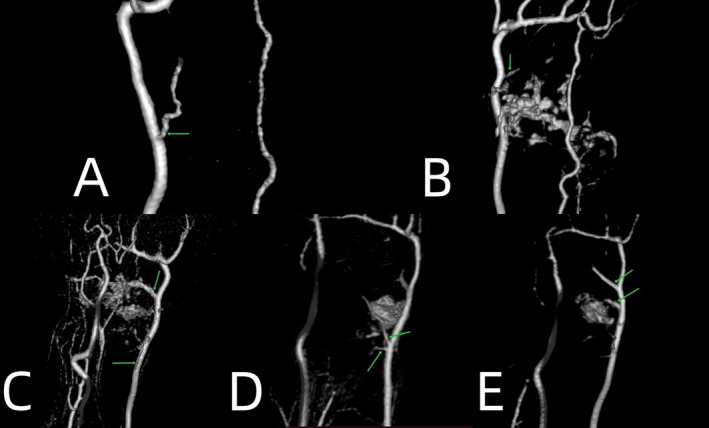

Methods: This was a prospective study. Between 2022 and 2023, contrast-enhanced magnetic resonance angiography and gadolinium-enhanced magnetic resonance imaging were performed in 32 patients (28 males and 4 females) with scaphoid fractures. The average age was 35 years (ranges: 15-74 years). We observed the accumulation and filling time of contrast media, and measured the diameters of extraosseous arteries as well as the signal intensity of intraosseous perfusion. The Mann-Whitney U-test, student's t-test, and Friedman test were used, respectively.

Results: 31 of 32 patients showed contrast media accumulation in the wrist joints on the affected sides. The filling time of contrast media on the affected sides was 5.6 (6.05-1) s quicker than on the healthy sides. The diameters of the radial arteries on the affected side increased by 12.8% (SD, 18.4%) compared to those on the healthy side (p = 0.002). All the patients had visible scaphoid nutrient arteries originating from the radial arteries on the affected side. The number of visible arteries on the healthy side was lower. Blood supply to the scaphoid was not related to the patient's sex, injury side, or fracture site. The increase in blood supply at the proximal fragment in older patients was less than that in young individuals (p = 0.015). Blood supply to the proximal and distal fragments of the scaphoid increased after fracture (p < 0.05). Within 1 month after the fracture, the increase in blood supply at the proximal fragment was less than that at the distal fragment, and it increased significantly after 1 month (p = 0.014). However, long-term nonunion (more than 4 years) leads to a decrease in proximal blood supply.